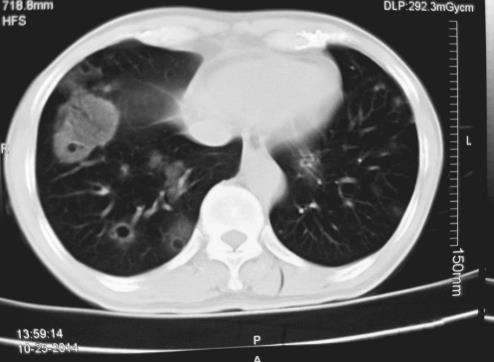

现病史:患者2014年9月在戴有强烈油漆气味义齿约10天后出现咯血,初始为痰中带少量鲜红色血液,2~3口/日,未给予重视,后痰中带血量逐渐增多至5~6口/日,且血量与痰量相当,偶感咽痒,无发热、牙周肿痛、乏力、盗汗,无胸痛、呼吸困难、喘息,偶有反酸,无恶心、呕吐、便血等,无皮疹、关节肿痛、肌痛、口眼干燥、反复发作口腔溃疡、光过敏等,一直未给予诊治。2014年10月25日觉咯血无好转就诊于社区医院,行胸部CT示“双肺散在大小不等的薄壁空腔样病灶,周围可见磨玻璃渗出影”(图1),后又于某三甲医院完善部分相关化验,但未明确病因,未给予治疗,10月28日为求进一步诊治入住我科。

图1 2014年10月25日胸部CT

双肺散在大小不等的薄壁空腔样病灶,周围可见磨玻璃渗出影